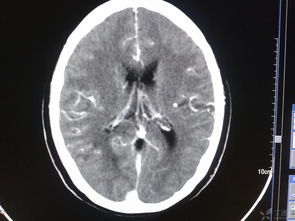

頭部損傷后常會(huì)發(fā)生繼發(fā)性顱內(nèi)損傷,其中最為嚴(yán)重的是顱內(nèi)血管破裂,形成顱內(nèi)血腫。

顱內(nèi)血腫形成后會(huì)使顱內(nèi)壓增高,使腦組織發(fā)生缺血、缺氧、水腫,顱內(nèi)壓力逐步增高,迫使部分腦組織發(fā)生移位而被擠進(jìn)顱內(nèi)生理孔道,形成危及生命的腦疝。 頭部受傷在天災(zāi)與人禍、戰(zhàn)爭(zhēng)與和平、生活與勞動(dòng)中均十分常見(jiàn),其病情危急,變化無(wú)常,后果嚴(yán)重。

顱內(nèi)血腫形成后會(huì)使顱內(nèi)壓增高,使腦組織發(fā)生缺血、缺氧、水腫,顱內(nèi)壓力逐步增高,迫使部分腦組織發(fā)生移位而被擠進(jìn)顱內(nèi)生理孔道,形成危及生命的腦疝。由于傷者家屬甚至一般醫(yī)護(hù)工作者對(duì)顱內(nèi)血腫和腦疝的發(fā)生規(guī)律、臨床表現(xiàn)和危害性缺乏深刻了解,或因傷后過(guò)早進(jìn)行腦CT掃描(其時(shí)出血尚未發(fā)生,血腫尚未形成),對(duì)傷員觀察欠仔細(xì),延誤診斷和治療,結(jié)果發(fā)生傷員不幸死亡的悲劇。

此為家人警惕性高、觀察到病情變化及時(shí)復(fù)診、醫(yī)生及時(shí)診斷并手術(shù)成功的典型病例。 目前診斷顱內(nèi)血腫最可靠最快捷的手段是CT掃描,它能在數(shù)分鐘內(nèi)清晰地顯示出血部位、血腫大小和伴隨的其他情況。

顱內(nèi)血腫若能及時(shí)診斷和手術(shù),病人是可以完全康復(fù)的。